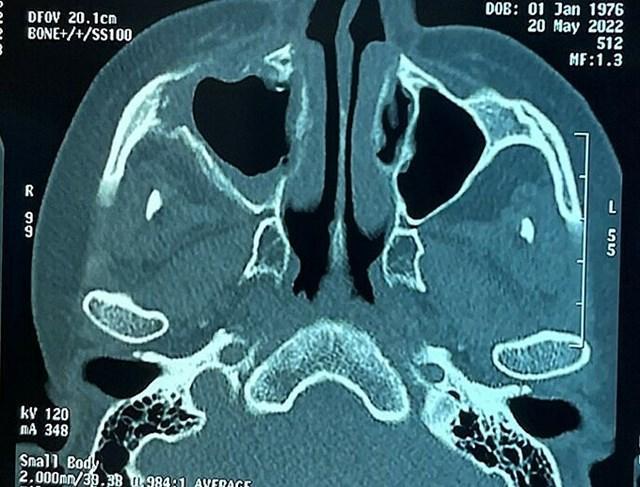

Phim chụp bệnh nhân bị hoại tử xương sọ (Ảnh: Bệnh viện Chợ Rẫy) |